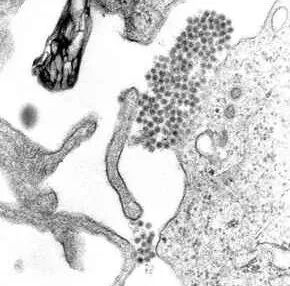

登革热病毒电镜下的形态

登革热是由一种黄病毒属的病毒引起,其下包括四种不同,但又密切相关的病毒血清型(DEN-1、DEN-2、DEN-3 和 DEN-4)。从感染中恢复提供对该特定的血清型终身免疫。然而, 恢复后对其他血清型的交叉免疫只是局部和暂时的。其他血清型的后续感染 (继发感染) 会增加患严重登革热的风险。